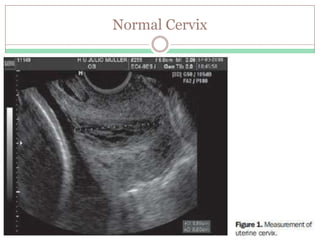

Normal Cervix

Low Risk (> 3.0 cm)

 LOW risk of preterm birth.

 FFN testing NOT mandatory.

 Observe for 4 to 6 hours to confirm fetal well-being.

 Reactive nonstress test

 Rule out abruption

 Rule out Infection.

 Rule out Cervical change

 Arrange follow-up in one to two weeks

 Give PTL instructions

 Bleeding, rupture of membranes, decreased fetal activity